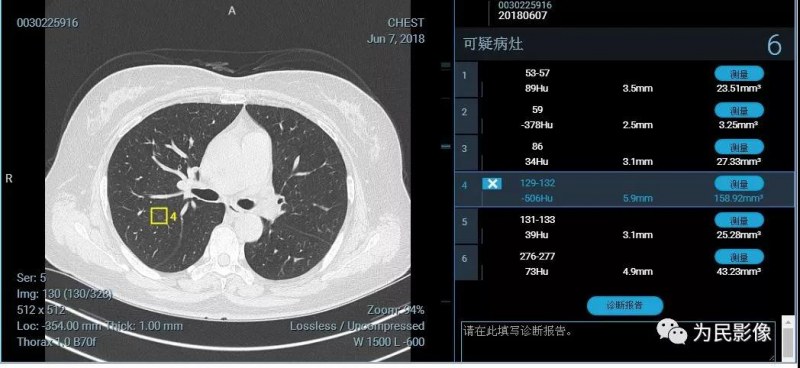

在肺結(jié)節(jié)篩查中,人工智能更多充當(dāng)醫(yī)生的第二雙眼睛。我們都知道,高分辨CT包含幾百幅圖像,人眼識(shí)別很容易漏診。AI軟件可以很快幫助醫(yī)生發(fā)現(xiàn)結(jié)節(jié),并檢測(cè)結(jié)節(jié)相關(guān)信息—密度、大小等,進(jìn)而醫(yī)生可以通過(guò)相關(guān)特點(diǎn)進(jìn)行判斷,防止醫(yī)生漏診并明顯提高工作效率。

(以上兩例患者憑醫(yī)生肉眼很容易漏診,人工智能發(fā)現(xiàn)的微結(jié)節(jié)均需要隨診復(fù)查。)